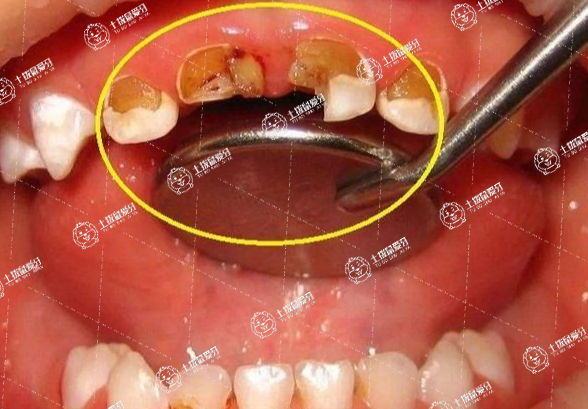

在缺牙后,牙友們選擇全瓷牙可以說是口腔門診一種快速、有效的修復(fù)牙齒方法,全瓷牙也成為很多牙友們選擇的修復(fù)方式,不過,對于全瓷牙修復(fù)過程中,很多人會比較在意是否能夠刷醫(yī)保,全瓷牙可以刷醫(yī)保嗎?這或許是牙友們比較在意的事情,接下來,我們一起來了解一下。

全瓷牙是不可以進(jìn)醫(yī)保的,一般這也是沒有醫(yī)保的項目的,你可以去詢問一下看看,烤瓷冠是目前非常常用的一種修復(fù)牙齒缺失、缺損的方法,它的美觀度及舒適度都是非常高的。但是一般來說,烤瓷冠的費(fèi)用是不能夠進(jìn)行醫(yī)保報銷的,因為它并沒有納入醫(yī)保范疇。

一般情況而言,戴牙冠不可以報銷。牙冠可以用全瓷牙,在口腔內(nèi)是很耐腐蝕的,并不會因為唾液或者食物而產(chǎn)生腐蝕,非常的耐用,而且生物相容性非常好,沒有任何毒副作用。一般來說,10年以后粘結(jié)劑在口腔中會出現(xiàn)溶解的情況,導(dǎo)致全瓷牙和牙齒之間不密合,需要及時更換。一般需要做烤瓷牙,盡量選擇三顆,這是更穩(wěn)固的方式。術(shù)后要注意口腔的衛(wèi)生,不要吃過于堅硬的食物,例如骨頭,螃蟹。飲食清淡,不要辛辣,更不要抽煙喝酒。